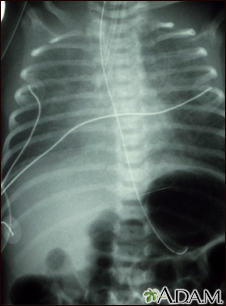

Totally anomalous pulmonary venous return - X-rayBackTotally anomalous pulmonary venous return - X-rayTotally anomalous pulmonary venous return (TAPVR) is a form of congenital heart disease. This x-ray shows an enlarged heart, a large liver, and increased pulmonary vascularity. E-mail FormEmail ResultsName:Email address:Recipients Name:Recipients address:Message: